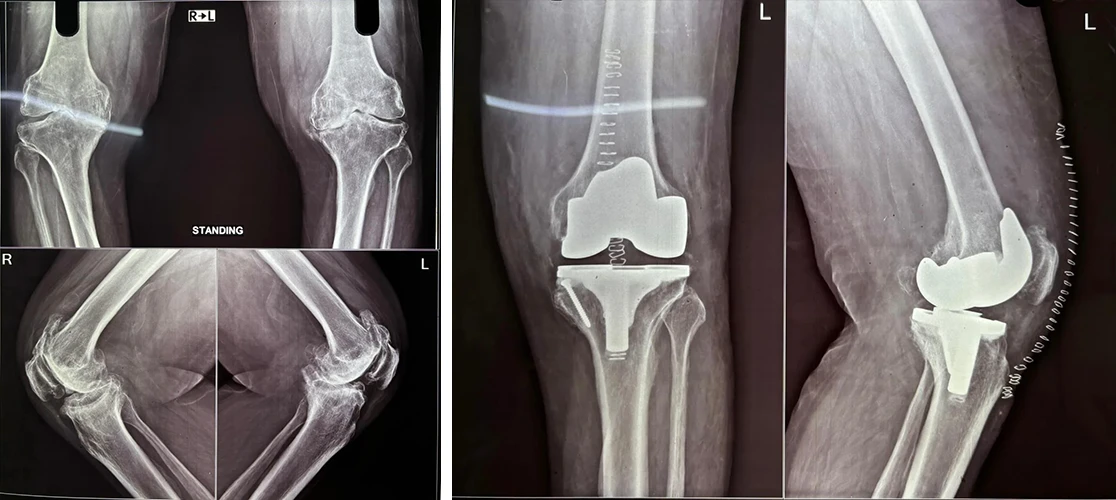

Total Knee Replacement

Are you having pain in your knees? Look no further, because Dr. Sanyal is the best choice for you. He specialises in total knee replacement surgery, offering you a solution to regain your mobility and live pain-free.